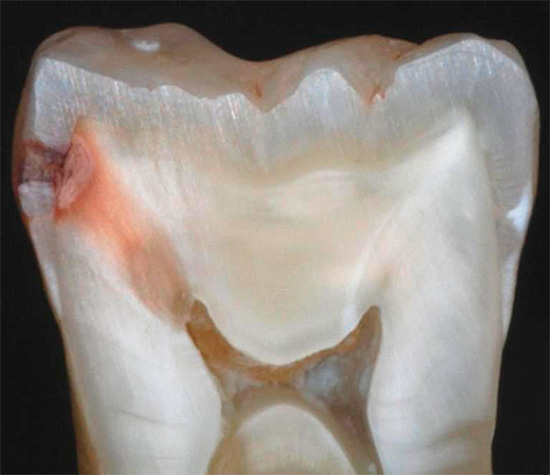

La foto sotto mostra la carie nascosta nel dente estratto (situato sulla superficie di contatto, cioè nel punto di contatto con il dente adiacente). L'area interessata ha raggiunto la camera pulpare: